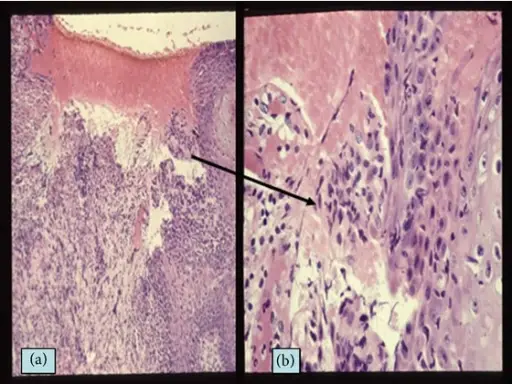

Squamous Cell Carcinoma

Squamous cell carcinoma (SCC) is the second most frequently diagnosed cancer worldwide.

Squamous cell carcinoma (SCC) accounts for about 30% of cancer cases in men and 20% of cases in women.

Two important risk factors for squamous cell carcinoma (SCC) are alcohol and tobacco use.

Invasive squamous cell carcinoma (SCC) may develop from oral leukoplakias and erythroplakias, which are precancerous diseases.

Although they can appear anywhere in the oral cavity epithelium, these lesions typically grow at the mouth’s floor.

Histologically, squamous cell carcinoma (SCC) is identified by alterations in the stratified squamous epithelial layers, such as invasion into the underlying connective tissue and hyperkeratosis, parakeratosis, acanthosis, keratin pearls, and dysplasia.